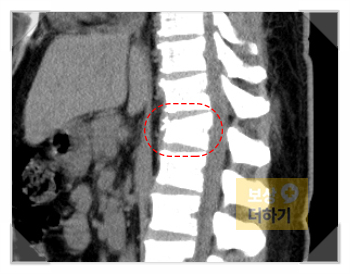

흉추12번 압박골절 (S22090)

정밀 검사에서 나온 결과는 흉추12번 압박골절이었습니다. 흉추 12번은 허리 바로 위쪽에 위치해 있으며, 상체 하중을 직접적으로 받는 부위라 압박 정도에 따라 장기적인 통증과 운동 제한이 남을 수 있습니다.

흉추 12번 압박골절 척추뼈가 눌려 압박되는 골절로, 낙상이나 추락 시 주로 발생 통증과 함께 허리를 굽히거나 펴는 동작에 제한이 생김

「보상 더하기」에서는 사고 상황을 구체적으로 검토하고 유사 사례에 대한 판례들을 근거로 이 00 님께 유리한 결과를 이끌어냈습니다. 또한 흉추12번 압박골절에 대해 맥브라이드 방식의 장해 평가를 진행하였는데요. 압박율과 후만각을 측정하여 32%, 영구장해 소견을 받을 수 있었습니다. 이를 근거로 상실수익액, 위자료 등 산정, 마침내 합당한 보상이 이루어질 수 있었습니다.